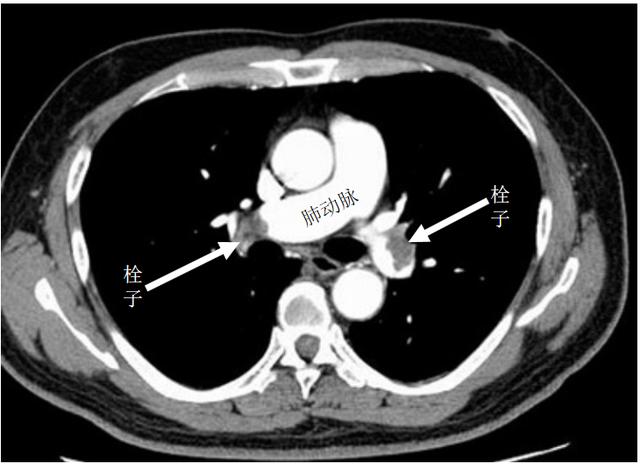

应该说,CT增强扫描可当大任。它扫描速度快、图像清晰、几乎无创,能清楚地显示肺动脉栓塞的部位、形态和范围,还能得到肺血流灌注信息以及肺血管的走行、分布情况,从而对治疗方案的选择和疗效评价提供可靠的影像学证据。

增强CT显示肺动脉栓塞